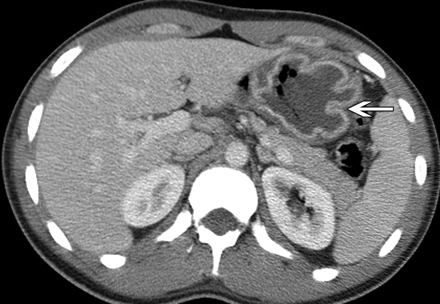

Appearance of hepatic abscess

usually has ill-defined margins with perilesional edema